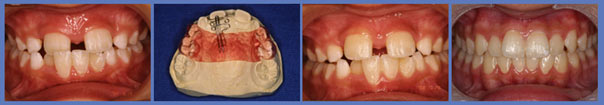

子供達を健康で綺麗な歯並びの永久歯列に誘導していくことを咬合育成と言います。開業時から来院していた子供達を見ていて、どうしたら綺麗な歯並びにできるのかを研究してきました。最近その成果が上がるようになり多くの子供達が健康できれいな歯並びをもった大人になって来院するようになっています。対外的にも「講演・論文」のページにあるように各地の歯科大学や歯科医師会からその分野の講演を依頼されるようになり、いつのまにか須貝歯科医院の得意分野になってしまいました。永久歯への生え替わりの時期が最も重要な時期です。簡単な装置で歯並びを改善していくのですが患者さんによっては矯正専門医に紹介しなければならないケースもあります。その時は地元の信頼できる矯正専門医をご紹介しています。

上の前歯は下の前歯より前にないといけませんが、前歯の生え替わりの時に1本逆に生えてきました。そのままではきれいな歯並びにはなりそうもありません。この時が治療のタイミングです。簡単な矯正装置で改善しただけでその後きれいな永久歯列になりました。